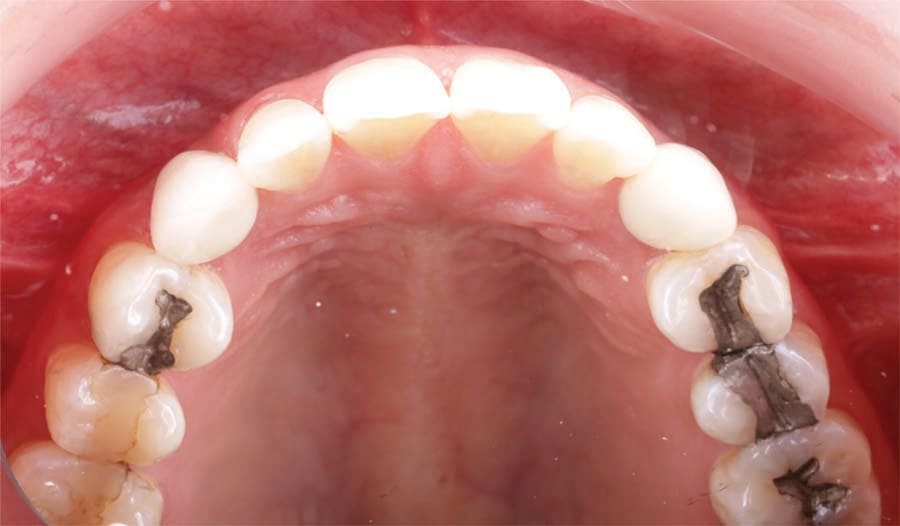

A 31-year-old Asian female presented for a consult. Her medical history was reviewed, and no health issues were noted. She indicated her last dental visit was 2 years ago and her chief complaint was that her deciduous canines felt loose and she was unhappy with her smile (Figure 1). Examination noted fair oral hygiene with light generalized calculus and moderate bleeding in the posterior with 4 mm probing on the molars. The deciduous canines were present bilaterally in the maxilla which were grade 1+ mobile (Figure 2). Cervical caries was noted on both deciduous teeth on the facial and also the distal of the left deciduous canine (Figure 3). Tooth No. 28 (right mandibular first premolar) was noted to be missing. The patient indicated the missing bicuspid never developed and the deciduous molar was lost in her teens. Physical examination noted a concavity in the vestibule apical to the gingival margin at both canine sites. A panoramic and bitewing radiographs were taken to evaluate the dentition and arches (Figure 4). Radiographically it was confirmed that the permanent maxillary canines were not present nor was the mandibular bicuspid. Further, significant resorption of the roots of the deciduous canines was noted.